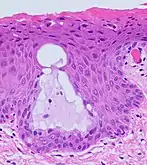

The endocervical mucosa is about 3 mm (0.12 in) thick and lined with a single layer of columnar mucous cells. It contains numerous tubular mucous glands, which empty viscous alkaline mucus into the lumen.[4] In contrast, the ectocervix is covered with nonkeratinized stratified squamous epithelium,[4] which resembles the squamous epithelium lining the vagina.[17]: 41 The junction between these two types of epithelia is called the squamocolumnar junction.[17]: 408–11 Underlying both types of epithelium is a tough layer of collagen.[18] The mucosa of the endocervix is not shed during menstruation. The cervix has more fibrous tissue, including collagen and elastin, than the rest of the uterus.[4]

.jpg.webp) The squamocolumnar junction of the cervix, with abrupt transition: The ectocervix, with its stratified squamous epithelium, is visible on the left. Simple columnar epithelium, typical of the endocervix, is visible on the right. A layer of connective tissue is visible under both types of epithelium.

The squamocolumnar junction of the cervix, with abrupt transition: The ectocervix, with its stratified squamous epithelium, is visible on the left. Simple columnar epithelium, typical of the endocervix, is visible on the right. A layer of connective tissue is visible under both types of epithelium. Transformation zone types:[19]

Transformation zone types:[19]

Type 1: Completely ectocervical (common under hormonal influence).

Type 2: Endocervical component but fully visible (common before puberty).

Type 3: Endocervical component, not fully visible (common after menopause).

In prepubertal girls, the functional squamocolumnar junction is present just within the cervical canal.[17]: 411 Upon entering puberty, due to hormonal influence, and during pregnancy, the columnar epithelium extends outward over the ectocervix as the cervix everts.[15]: 106 Hence, this also causes the squamocolumnar junction to move outwards onto the vaginal portion of the cervix, where it is exposed to the acidic vaginal environment.[15]: 106 [17]: 411 The exposed columnar epithelium can undergo physiological metaplasia and change to tougher metaplastic squamous epithelium in days or weeks,[17]: 25 which is very similar to the original squamous epithelium when mature.[17]: 411 The new squamocolumnar junction is therefore internal to the original squamocolumnar junction, and the zone of unstable epithelium between the two junctions is called the transformation zone of the cervix.[17]: 411 Histologically, the transformation zone is generally defined as surface squamous epithelium with surface columnar epithelium or stromal glands/crypts, or both.[20]

After menopause, the uterine structures involute and the functional squamocolumnar junction moves into the cervical canal.[17]: 41

Nabothian cysts (or Nabothian follicles) form in the transformation zone where the lining of metaplastic epithelium has replaced mucous epithelium and caused a strangulation of the outlet of some of the mucous glands.[17]: 410–411 A buildup of mucus in the glands forms Nabothian cysts, usually less than about 5 mm (0.20 in) in diameter,[4] which are considered physiological rather than pathological.[17]: 411 Both gland openings and Nabothian cysts are helpful to identify the transformation zone.[15]: 106